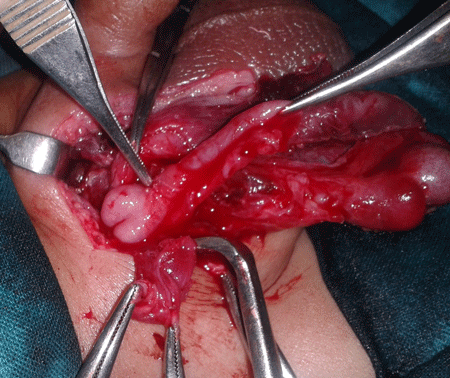

A 4-month-old infant presented with a history of reducible right inguino-scrotal swelling since birth which had become irreducible for 4 days prior to presentation. It was associated with non-bilious vomiting and fever. On examination the child was irritable and local examination revealed an irreducible swelling in right inguino-scrotal region with redness of overlying skin and raised local temperature. Right testis was not separately appreciable due to overlying edema. Abdomen and pelvis lateral view roentgenogram showed gas filled bowel loops in the abdomen and a gas shadow in the scrotum (Fig.1). A diagnosis of strangulated inguinal hernia was initially made. After optimization of his general condition, inguino-scrotal exploration was done. About 10 cc foul smelling yellow pus was drained. The appendix was found in the hernial sac, perforated at the level of proximal third of shaft with gangrenous distal portion. The base of appendix and cecum were healthy and right testis was viable (Fig. 2). An appendectomy was performed. The stump and cecum were reduced and herniotomy done. Wound was washed thoroughly and closed primarily. Postoperative course was smooth, except for wound infection which was managed conservatively. At follow-up the infant is doing fine.

There is no consensus on management protocol in cases of AH. Inflammatory status of appendix usually determines the approach.[8] In an AH with a non-inflamed appendix, only herniotomy is performed, although some recommend appendectomy especially in the cases of left sided AH.[3,4] With evidence of acute inflammation, trans-herniotomy appendectomy should be done.[1,9] In the index case, inflammation, ischemia, subsequent perforation and peri-appendicular abscess formation occurred in the portion lying outside the deep ring, therefore, only trans-herniotomy appendectomy was performed. A high mortality rate of 14-30% has been reported especially in the cases of perforated appendicitis with or without peri-appendicular abscess and peritonitis.[9]

Figure 2:Per operative picture showing perforated appendix in the hernial sac. |